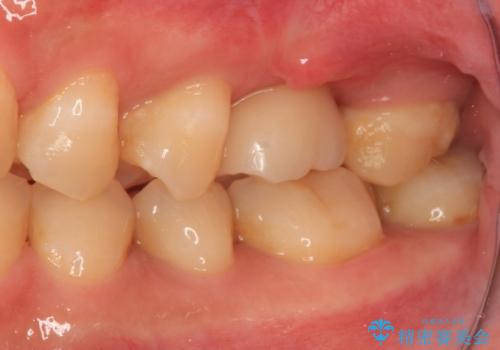

割れてしまった奥歯 サイナスリフトによるインプラント補綴治療

- 近医にて歯が割れている可能性があると言われて来院された患者様です。

初診時の診察所見では、破折の可能性は低く、根管治療を前提とした治療にて説明をしておりました。